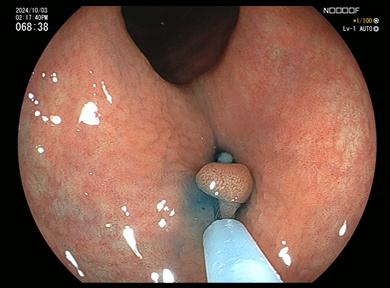

大腸ポリープ

通常光(白色光)

通常光では淡い発赤ですが

特殊光-1

同じところを空気量調整し特殊光LCIにて観察

特殊-2

同じところを特殊光BLIにて血管と表面構造を観察

ポリープ切除術

1

IS型といわれる大腸ポリープです。

2

スネアをポリープに引っ掛けます。

3

スネアの輪を絞ります。

4

ポリープを切除、血液のにじみはわずかです。